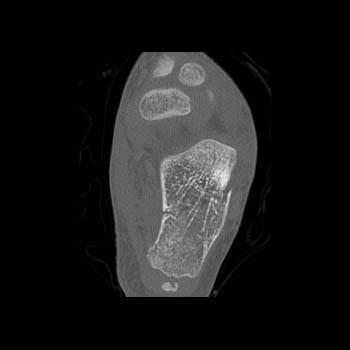

Foot Pathology: Calcaneal fractures

The calcaneus is the most commonly fractured tarsal bone. Calcaneal fractures are classified as intraarticular and extraarticular. The intraarticular fracturesaccount for 70-75% of calcaneal fractures and carry a worse prognosis. The inciting trauma is usually a fall or motor vehicle accident, and these fractures are bilateral in 10% of cases. Concomitant ipsilateral lower extremity fractures are present in 20-46% of cases, and spinal fractures in 10-30%. Extrarticular fractures (Figure: extraarticular fracture of calcaneus) account for 25-30% of calcaneal fractures, and are the sequela of a twisting injury. Anatomic regions affected include the anterior or medial process, the sustentaculum tali, the body or the tuberosity. Severe fractures are readily evident on conventional radiographs; however, CT is essential for elucidating the extent of injury. The intraarticulur fractures are often comminuted and may be displaced. CT is also used for follow up after fracture treatment. CT is very helpful for detecting fracture malunion or nonunion . In addition, the presence and extent of secondary osteoarthritis is readily detected by CT. Several features of intraarticular fractures which can be elucidated on CT have been shown to correlate with the outcome. A central depression fracture has a worse prognosis than a tongue-type fractures, but a better prognosis than a comminuted fracture. An unsatisfactory result is more likely in the setting of subtalar incongruity, decreased fibulocalcaneal space and osteoarthrosis of the talonavicular joint and the ankle.